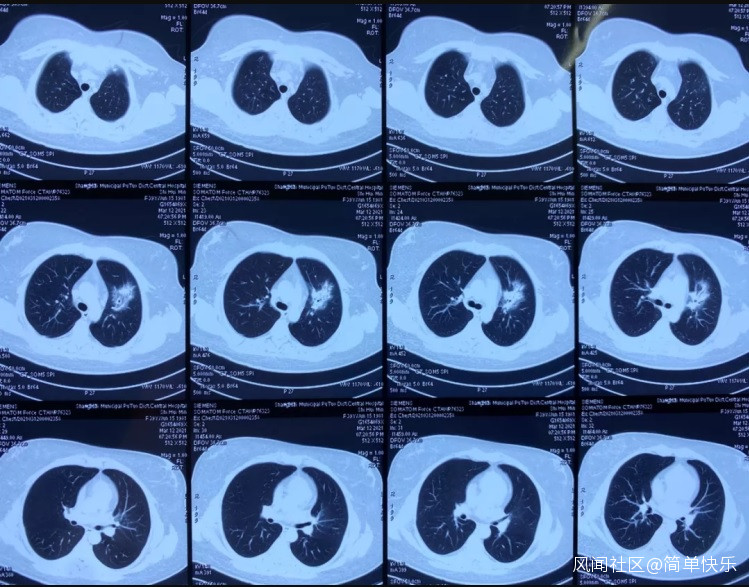

第二天,於女士依然是39-40℃的高熱,於是轉診到另一家醫院治療。經檢查,其白細胞以及感染指標C反應蛋白都是升高的,胸部CT顯示左肺上葉及右肺下葉炎症。進行抗生素治療後,效果依舊不好,仍然反覆發熱,而且開始出現胸悶、咳嗽、咳少量的白痰。